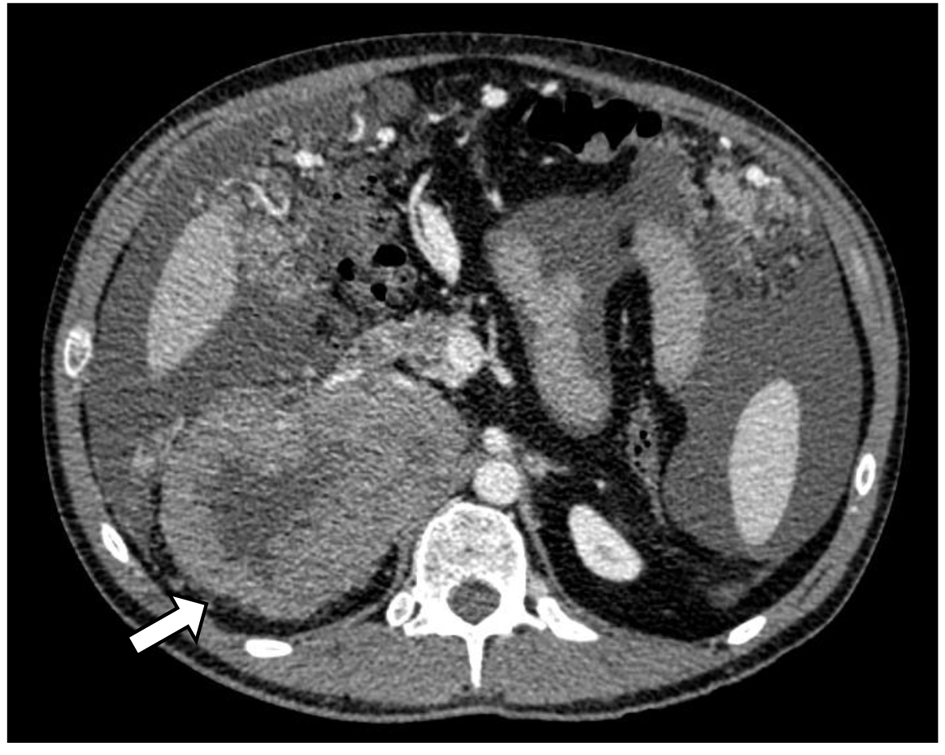

A 37-year-old man with no past medical history of hypertension or prior malignancy was admitted to the University Hospitals of Torrejon (Madrid, Spain) in July 2013 with worsening epigastric pain, decreased appetite, and 10 kg loss of weight over 6 months. His abdomen was mildly distended and on physical examination presented ascites. Computerized tomography (CT) (Fig. 1) revealed a huge heterogeneous adrenal tumor (13 cm in diameter) on the right side, compressing the inferior vena cava (IVC) and peritoneal carcinomatosis.

![]() Click for large image | Figure 1. CT scan of adrenocortical carcinoma showing necrotic right adrenal mass in close proximity to the body/tail of pancreas and third portion of the duodenum (white arrow). |